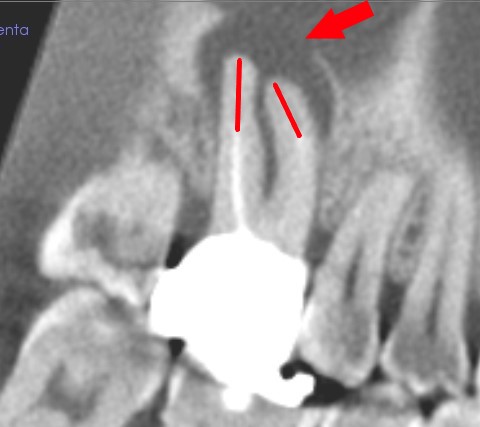

根管の穿孔による、歯周組織の骨吸収

これは、特別な、穿孔という例です。

根の横に、骨の溶けた部分があります。

曲がった根管を、直線的に削ったため、弯曲の内側に穴が開いたのでしょう。

患者さんは、根の不調は、抜くようになるとのことで、当院で治療なさいました。

(根の不調で、過去、抜かれたことあり)